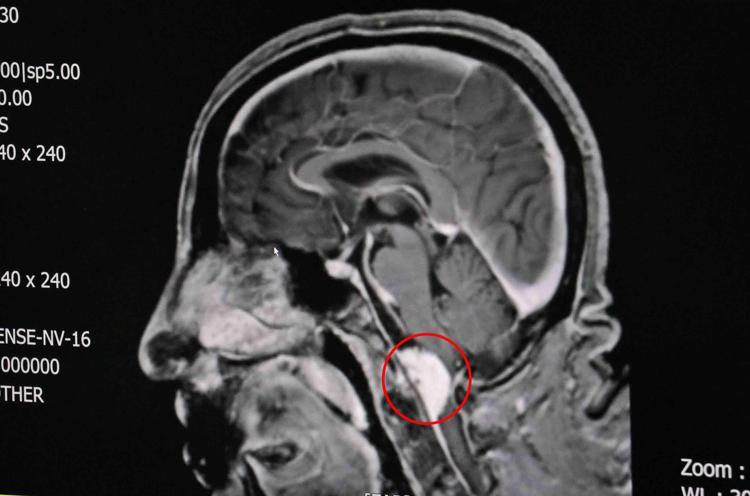

Beyin ve Sihir Cerrahisi Uzmanı Dr. Abdurrahim Taş, tarafından muayene edilen Başar’ın beyin sapının önündeki foramen magnum (Kafatasının alt kısmında bulunan boyun deliği) kısmında 4 santimetrelik tümör tespit edildi.

Beyin sapının önünde foramen magnumda 4 santimetrelik tümör tespit ettik. Hastaya ameliyat olması gerektiğini söyledik. Hasta ve yakınları düşündükten sonra bize geri döndüler, ameliyatı kabul ettiler. Yüksek riskli bir ameliyattı, bu sebeple hastaya riskleri anlatıp ameliyatını planladık. Ameliyatı yaklaşık 10 saat sürdü. Bu şikayetlerinin hemen hemen çoğunun gerilediğini gördük. Ameliyatı başarılı bir şekilde yapmamız bizi de hastamızı da çok mutlu etti” diye konuştu.